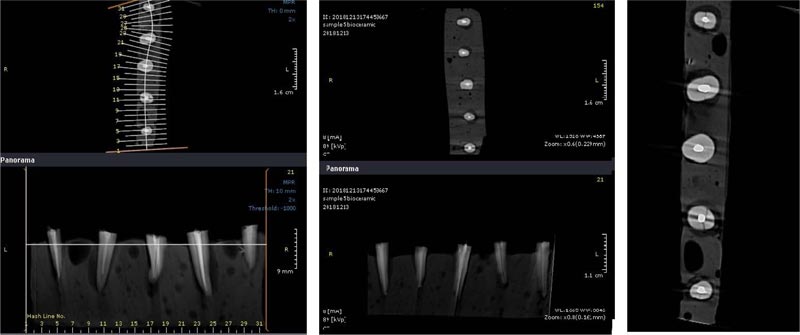

The apex of the prepared teeth was inserted into the wax, and then the teeth were placed in acrylic blocks (1 * 10 cm). A Cranex 3D CBCT device (Soredex, Tuusula, Finland) with 200 µm voxel size and 6 × 8 cm2 field of view (FOV) was used for scanning root fractures. Device settings were set to Kvp: 90, mA: 10, and time: 12 s. The images were then saved in DICOM format and evaluated using Ondemand 3D dental (Cybermed, Seoul, South Korea) software (Figs. 2 and 3). A 15-inch liquid crystal display monitor (Toshiba Satellite L40, Tokyo, Japan) with a 768 * 1367 pixel matrix was used for observation and interpretation of images in a dimly lit room with no time restriction. The images were assessed twice by an expert oral and maxillofacial radiologist and a dentist separately in two weeks. The two observers were allowed to adjust the brightness, contrast, and magnification of images to obtain the best visual results. All cross-sectional slices had 1-mm intervals and 0.5-mm thickness. Coronal, sagittal, and axial sections were used to detect VRF.